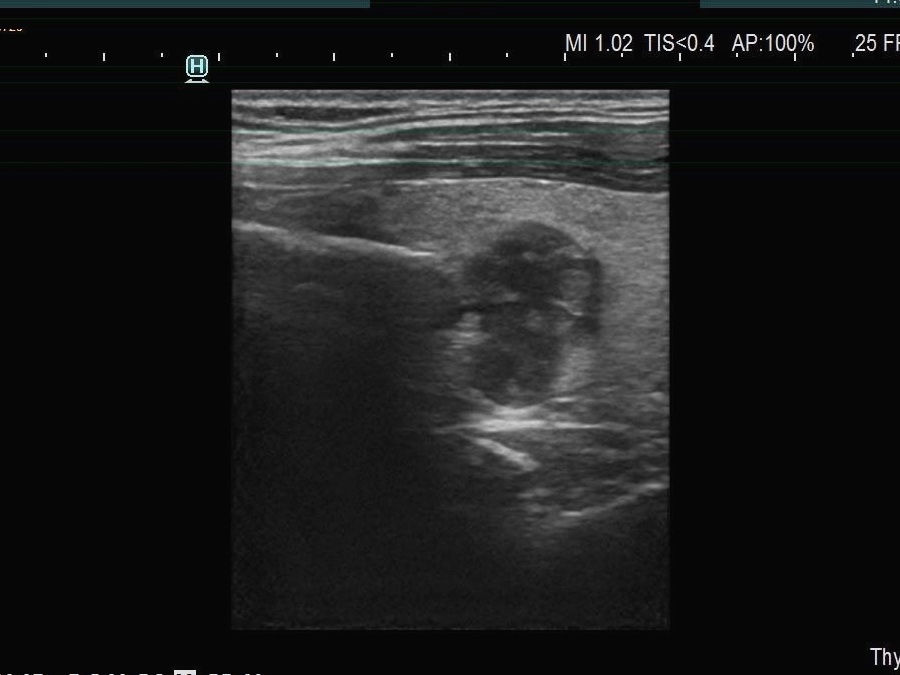

The echogenicity of the nodule - case 1740 (ultrasonographic picture 13)

Left lobe, longitudinal scan - with decreased frequency. If it is a mass composed of multiple nodules , then the ventral nodule has irregular borders. If this is one single nodule, then it shows taller-than-long shape, too.